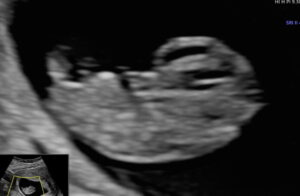

Vroege echo 2D

- 7 – 13 weken

- 2D echo van 10 minuten

- 2 zwart-wit fotoprints

- Na afloop van de echo ontvang je een selectie van de mooiste beelden en clips via de e-mail